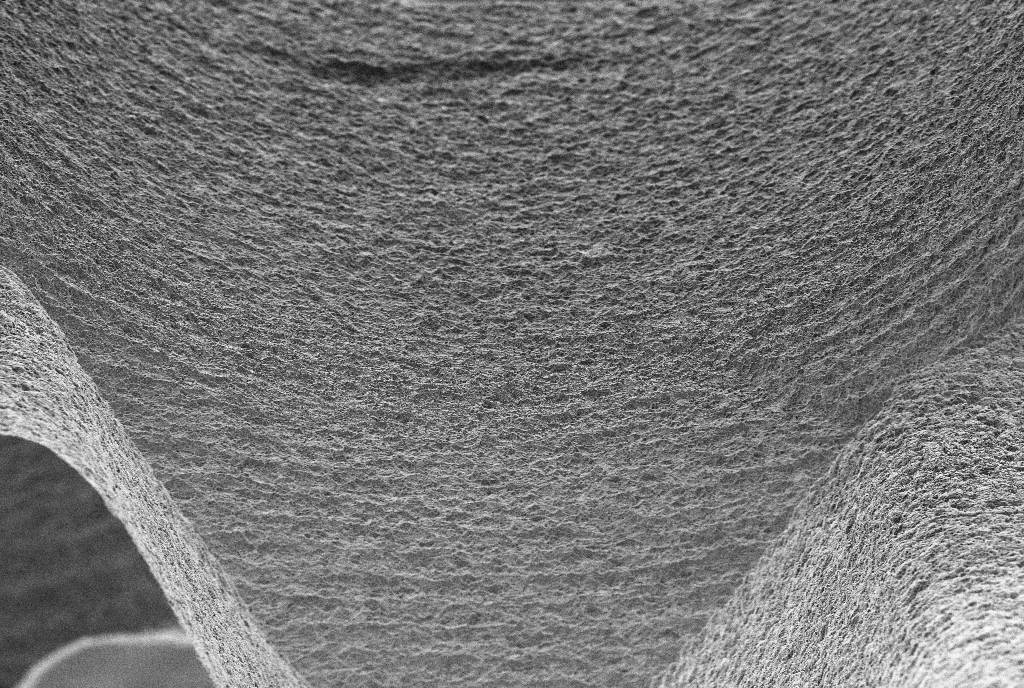

O SUPEX é um tratamento superficial que promove uma área de contato com o osso 100% maior do que os implantes com superfície lisa. Sua superfície rugosa, porém uniforme, é obtida através de um tratamento ácido sequenciado patentead

Esta superfície provê melhores condições de cicatrização e reduz o tempo de osseointegração.

Com esse tratamento conseguimos uma porosidade homogênea [micro e macro porosidade] ideais para a interação entre implante e tecido ósseo.